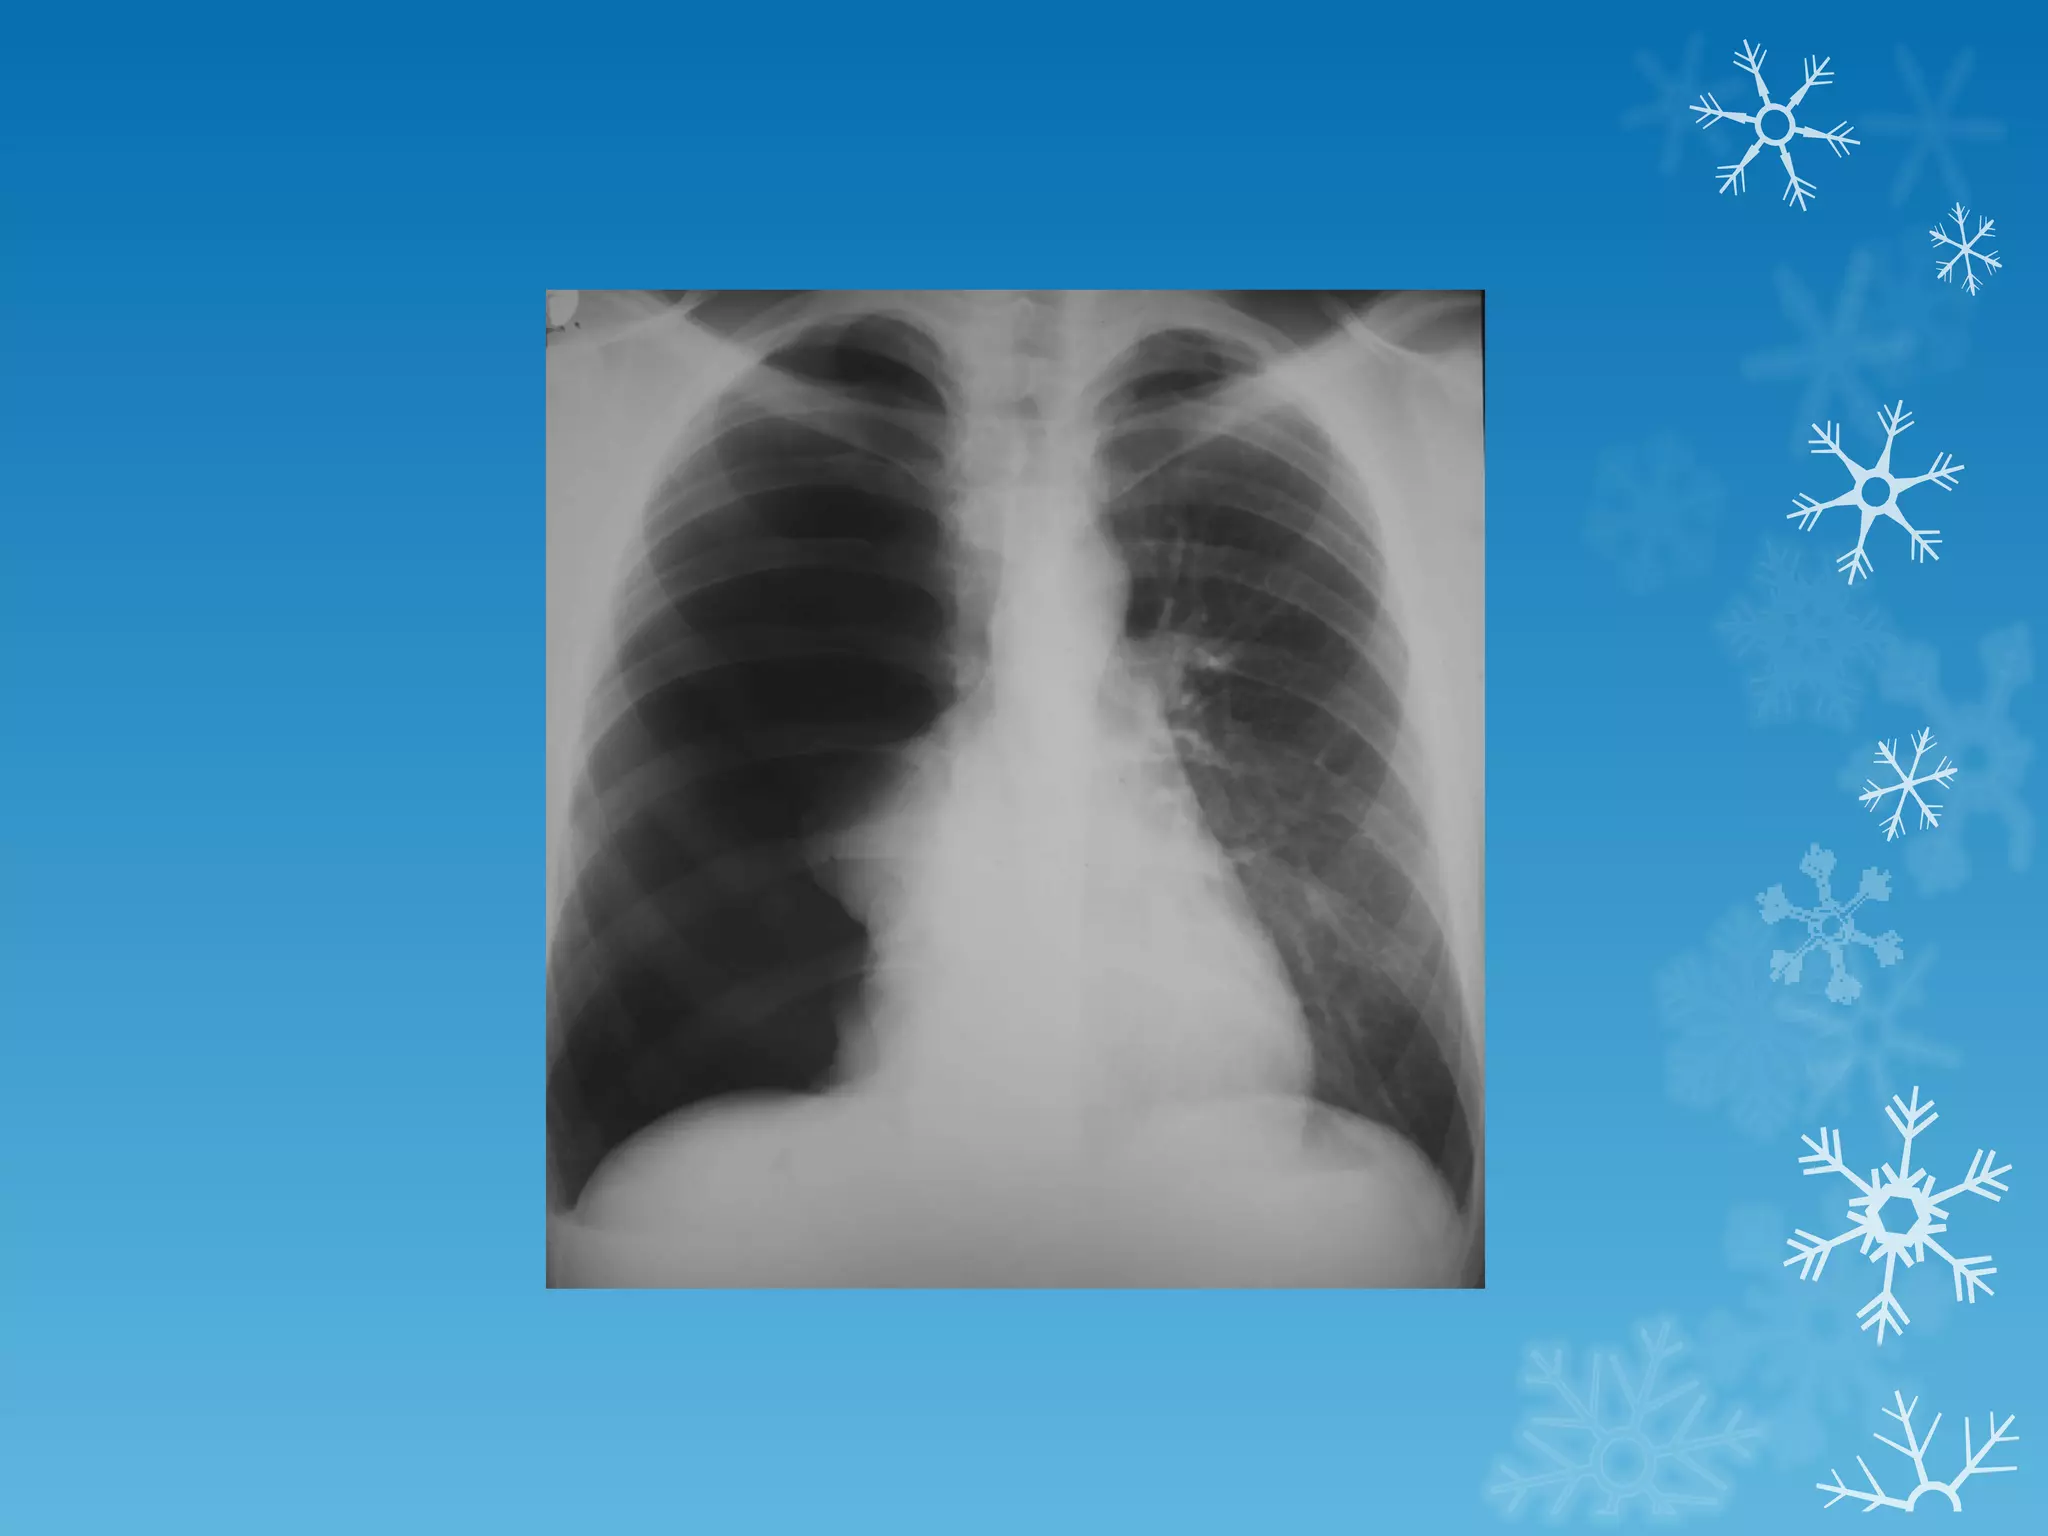

This document discusses chest x-ray interpretation and provides guidance on evaluating x-rays. It explains that tissue density determines how an x-ray beam penetrates, with denser tissues appearing whiter and less dense tissues appearing blacker. It also outlines different chest x-ray views and factors to consider like patient orientation, age, gender, and rotation. Abnormalities are described as appearing too white, too black, too large, or in the wrong place. The document stresses a systematic approach of identifying, localizing, describing lesions, and providing differential diagnoses.